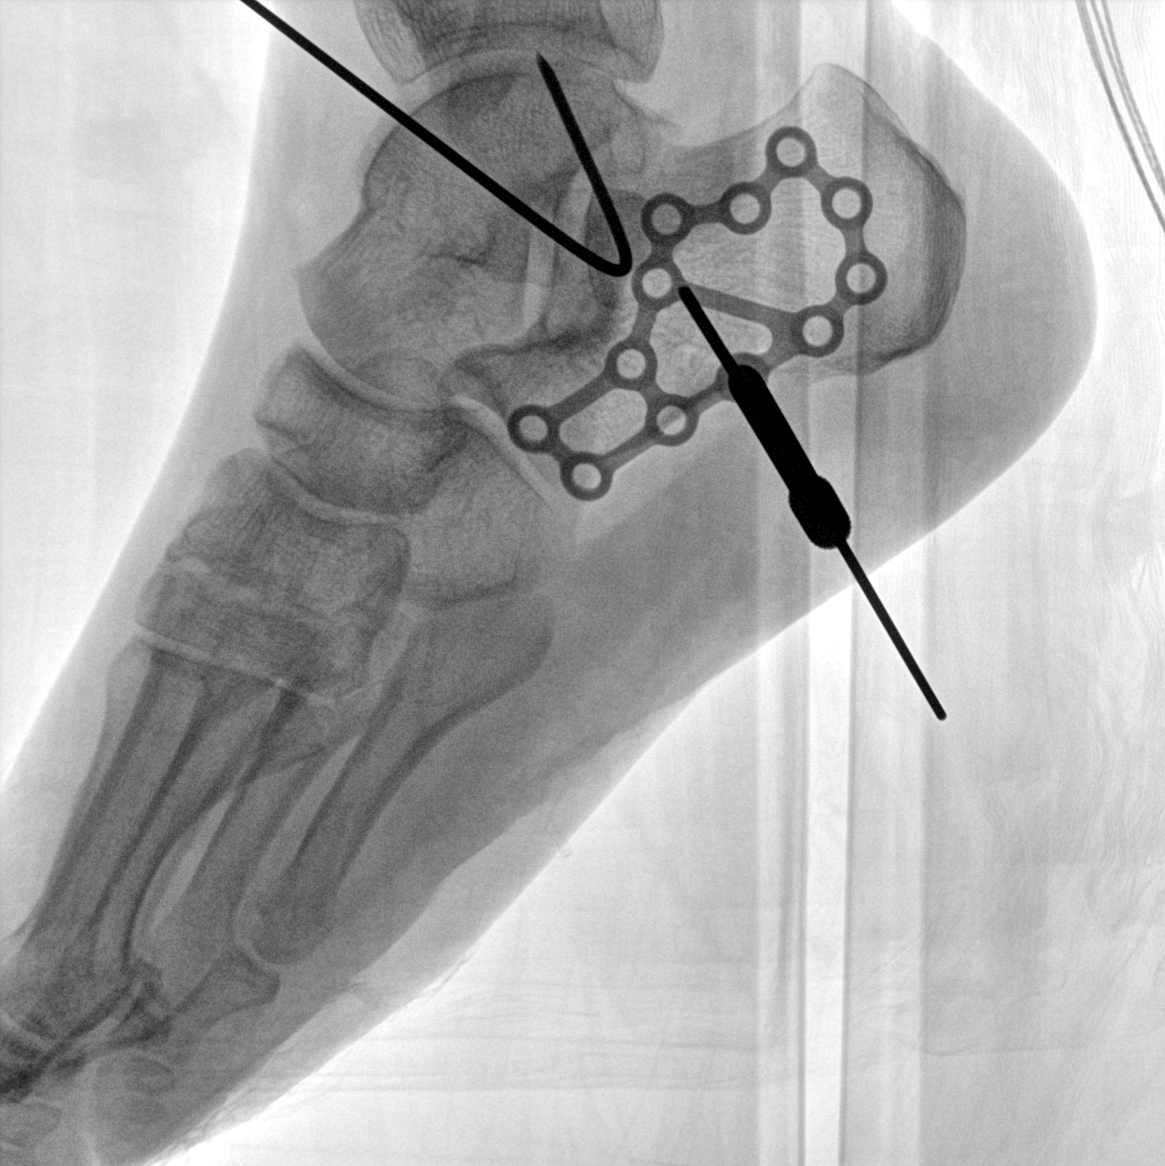

術(shù)中三維成像和橫斷面圖像提供多角度的手術(shù)診斷信息,輔助醫生進(jìn)行術(shù)中評估判斷,諸如骨折復位情況和內植入螺釘的尺寸和位置,輔助手術(shù)更好地完成。